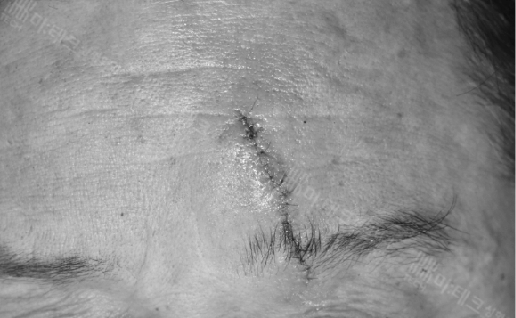

울산에서 전날 밤에 찢어진 후 아침 일찍 저희 병원을 찾아주셨습니다.

딱 봐도 ‘헉’ 하죠

맨눈으로 꿰매는 게 아니라 3배 확대경을 보면서 한 땀 한 땀 어긋나지 않게 봉합합니다.

피부에 봉합하는 가장 가는 실로 말이죠.

실밥 제거 직후 사진입니다.